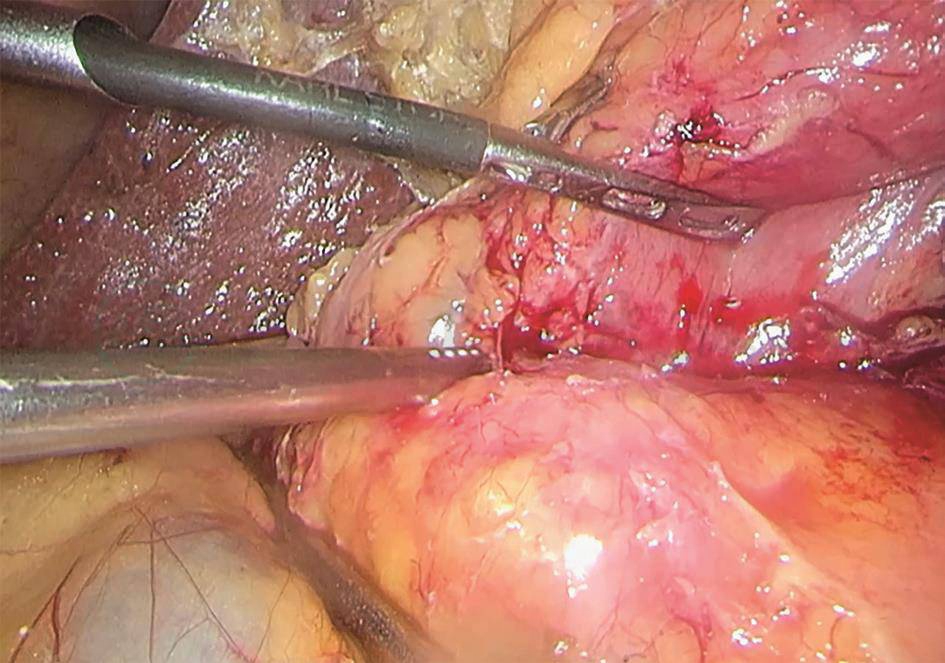

2020-03-30:行腹腔镜辅助胰十二指肠切除术(改良Blumgart胰肠吻合),术中见腹腔内无明显转移结节,胰头-十二指肠周围水肿呈硬块状,范围约8cm×8cm(图9)。切除标本后,可见:壶腹部有一1.5cm×1.5cm大小肿物,侵及胰腺及十二指肠,胆管及胰管内可见陈旧性积血(图10)。术中冰冻结果:胰腺中-低分化腺癌。常规病理结果:“壶腹部”胰胆管型中低分化腺癌,大小1.5cm×1.5cm,侵及十二指肠黏膜下层、胰腺实质(图11)。神经、脉管累犯阳性,周围组织见大片液化坏死伴肉芽组织增生。淋巴结2/18。pTNM分期T3aN1M0。免疫组化:CK7(-)、CK20(-)、CDX2(弱+)、P53(突变型)、Ki-67(约30%)。

图9 胰头-十二指肠周围水肿明显

5.术中决策与困难

由于术前做了GDA栓塞,术中胰头-十二指肠周围水肿明显,当然这在预料之中。根据大量困难胰十二指肠切除术的经验,选择“Easy First”策略,将手术分解,胃、胆、空肠三个区域率先完成,做完Koche切口后主动中转开放手术,攻下水肿最为明显的胰头钩突区域的切除。事实证明,该策略极为明智,既降低了手术风险,又缩短了手术时间,减少了对患者的手术打击。